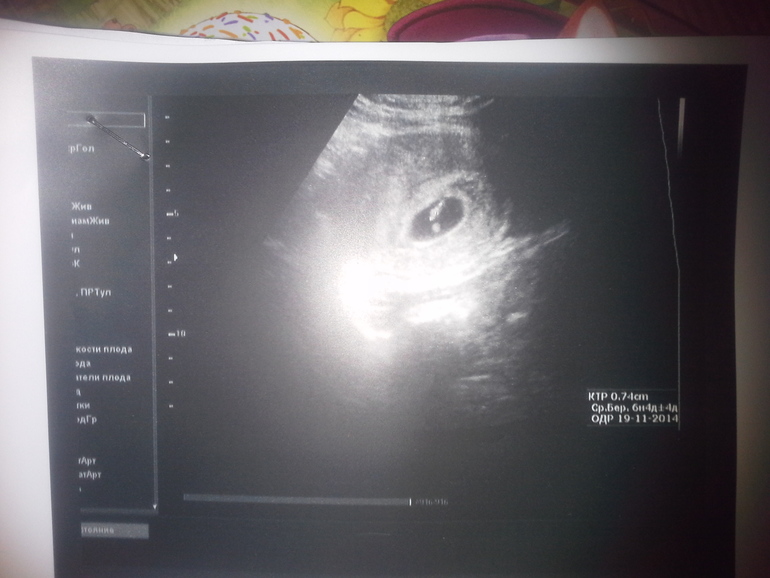

наше узи

Жду второго малышастика))Вчера были с мужем на узи, послушали сердечко, посмотрели кроху нашу))))

Да, я тоже как увидела, подумала об этом, потом почитала вердикт узистки, там написано 1 плодное яйцо! Вот и думай теперь, что это?)